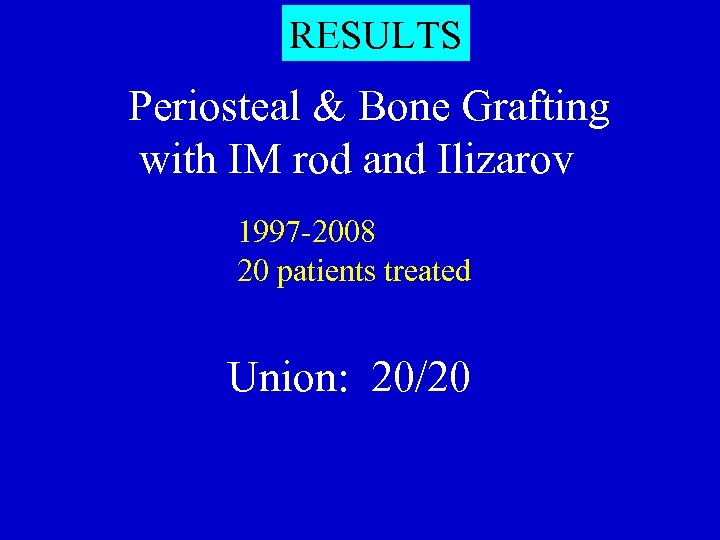

RESULTS Periosteal & Bone Grafting with IM rod and Ilizarov 1997 -2008 20 patients treated Union: 20/20